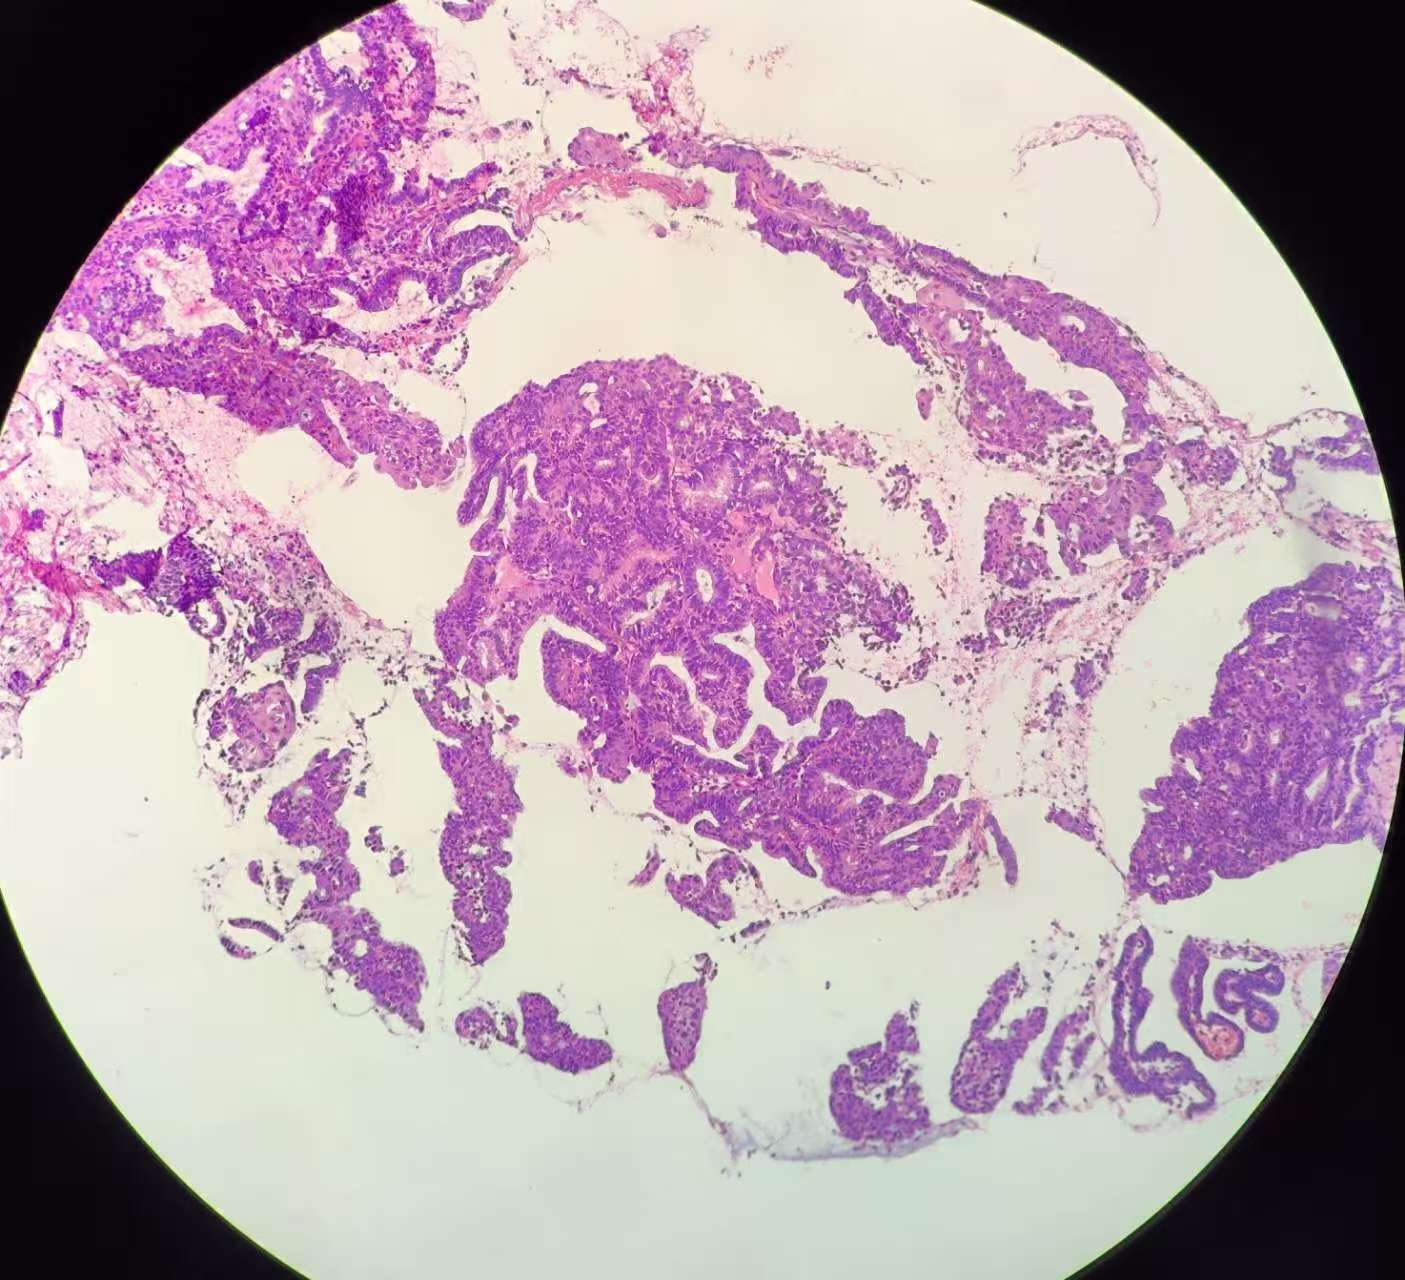

性别

女

年龄

51岁

临床诊断

子宫 内膜息肉?

一般病史

绝经三年,近期阴道出血,宫腔镜见后壁槽杂样组织,质脆

标本名称

子宫内膜诊刮

大体所见

灰红碎组织1堆

复杂性增生?部分区域腺体融合似成实性,癌?局部内膜腺体鳞化还是宫颈鳞上皮病变(第1张图和最后一张)?

考虑子宫内膜样腺癌,伴有鳞状分化。